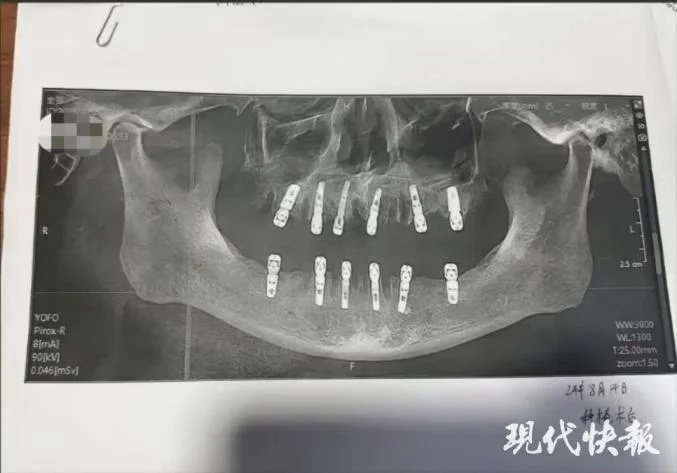

Người phụ nữ này đã đưa ra bằng chứng cho thấy cha cô đã nhổ 23 chiếc răng và trồng 12 chiếc răng mới trong một lần. Cô Shu cho rằng chính điều này là nguyên nhân khiến cha cô tử vong 13 ngày sau đó.

Theo cam kết chấp thuận thực hiện thủ thuật của bệnh nhân, cha của cô Shu thực tế đã nhổ 23 chiếc răng tự nhiên trước khi khoan 12 lỗ vào hộp sọ và xương hàm để trồng những chiếc răng mới. Tất cả những thủ thuật này được thực hiện trong cùng một ngày. Điều đó có nghĩa là ông đã phải chịu đựng cơn đau không thể tưởng tượng được sau khi thuốc gây mê hết tác dụng.